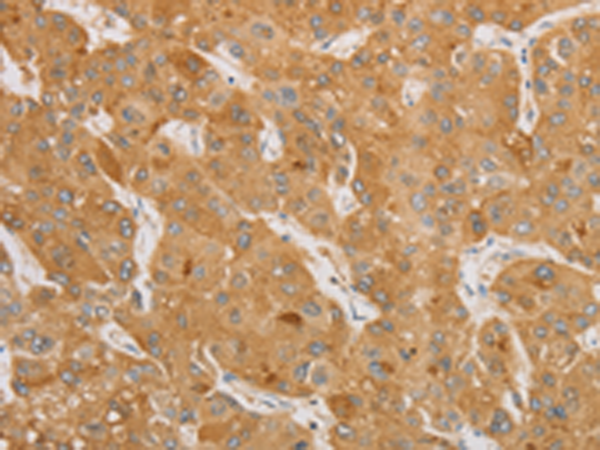

分类: 科研抗体货号: P00545别名: MPF; SMRP应用: IHC反应种属: Human